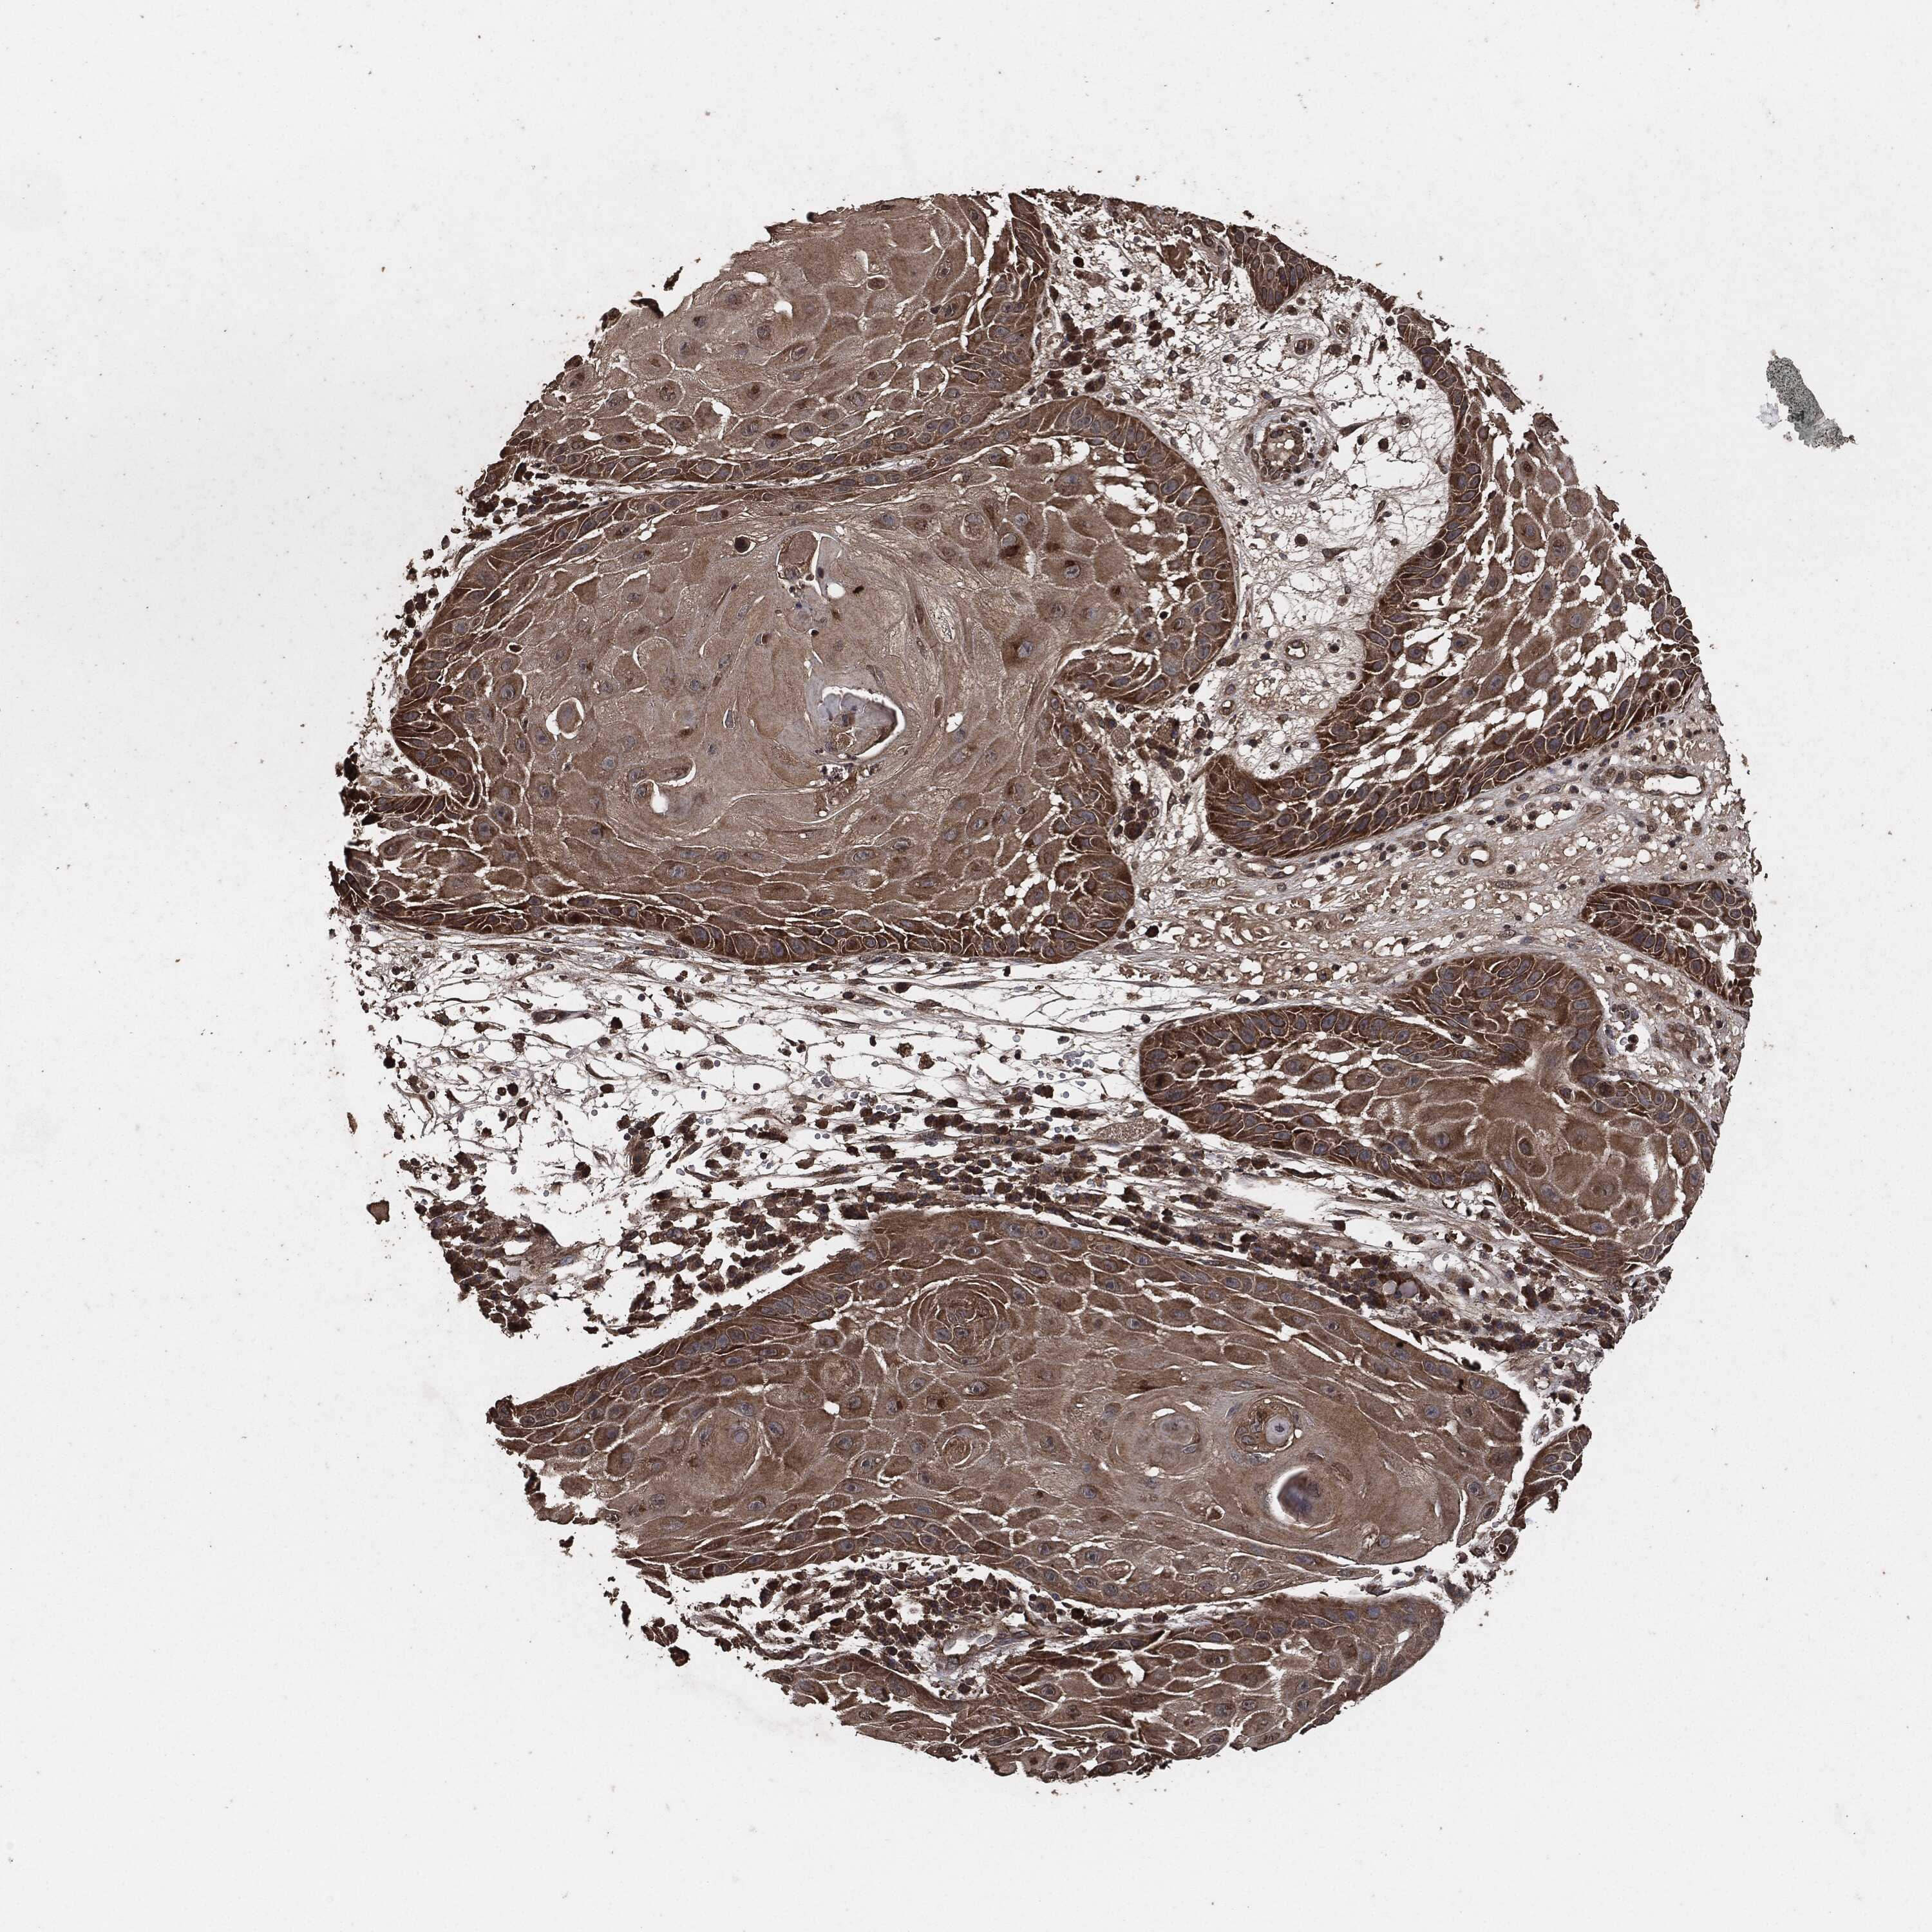

SKIN CANCER - Protein expressioni

A mouse-over function shows sample information and annotation data. Click on an image to view it in a full screen mode. Samples can be filtered based on level of antibody staining by selecting one or several of the following categories: high, medium, low and not detected. The assay and annotation is described here.

Each image is clickable and will lead to virtual microscopy that enables deeper exploration of all samples and also displays staining intensity scores, fraction scores and subcellular localization as well as patient and tissue information for each sample.

Antibody HPA064427

Antibody CAB021903

Staining

High

Medium

Low

Not detected

Intensity

Strong

Moderate

Weak

Negative

Quantity

>75%

75%-25%

<25%

None

Location

Nuclear

Cytoplasmic/membranous

Cytoplasmic/membranous,nuclear

Basal cell carcinoma

BCC, high aggressive

Squamous cell carcinoma, NOS